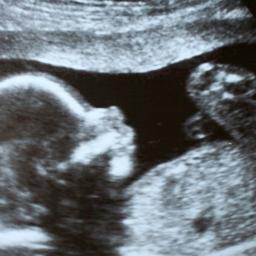

Werk samen, concurrentie helpt ongeboren kind niet

Om ongeboren kinderen goed te kunnen behandelen in de baarmoeder, is samenwerking onontbeerlijk, schrijven Jan van Lith, Dick Oepkes, Roland Devlieger en Peter Lindgren.